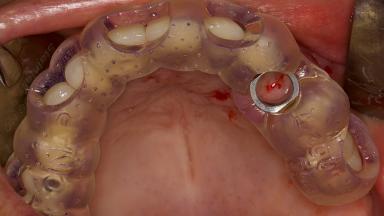

Digitally Guided Sinus Floor Elevation

In this short microlearning module on digitally guided sinus floor elevation, we delve into a specialized aspect of the digital workflow for implant-guided surgery, focusing on the use of digital guides in the sinus floor elevation technique.

• define the manufacturing process of digital guides for SFE

• explore the intraoperative use of digital guides in SFE